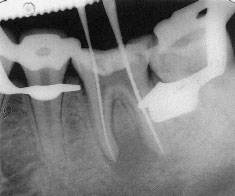

Обработка файлами производится по всей длине корневого канала до самой верхушки корня, а не далее верхушки. Главным этапом в обработке корневых каналов является определение их длины. Для этого, стоматолог сначала вставляет в каналы файлы и делает рентгеновский снимок, по которому и определяется длина корневых каналов.